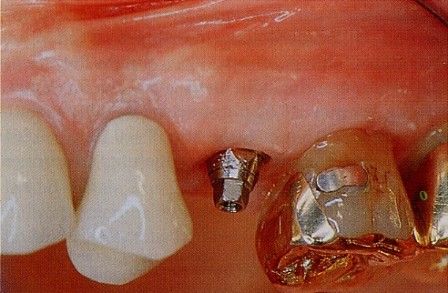

Endosteal implantlar - bu implantlar, cerrahi yöntemle, çene kemiğine direkt olarak implante edilirler. Çevredeki dişeti dokusu iyileştikten sonra, orijinal implanta bağlantı sağlayacak materyali takmak için ikinci bir operasyon gerekir. Son olarak, yapay diş (veya dişler) tek başına veya köprü ya da protez üzerinde grup halinde implanta takılır.

Subperiosteal implantlar - bunlar, dişeti dokusunun hemen altındaki çene kemiğine takılan metal bir çerçeveden oluşurlar. Dişeti iyileştiğinde, çerçeve çene kemiğine sabit hale gelir. Çerçeveye takılan materyaller, dişetlerinden dışarı çıkar. Endosteal implantlarda olduğu gibi, yapay dişler, daha sonra implantalara monte edilir.

İMPLANTLARIN YERLEŞTİRMESİ VE PROTEZ KADAR SÜRER? Cerrahi işlemin süresi yerleştirilecek implant sayısına ve hastanın koşullarına bağlı olarak yarım saat ile birkaç saat arasında değişebilir. Operasyondan sonra, implant ile kemiğin kaynaşması için (osseointegrasyon) 2-3 ay kadar beklenir. Daha sonra bu implantlar üzerine, birkaç seans süren bir uygulama ile protezler yerleştirilir. İmplantlar dişler çekildikten hemen sonra yerleştirilebilir mi? Evet,günümüzde bu mümkündür.İmplant diş çekimini takiben taze çekim boşluğu içerisine yerleştirilebilir.Buna “immediyat uygulama” denir.